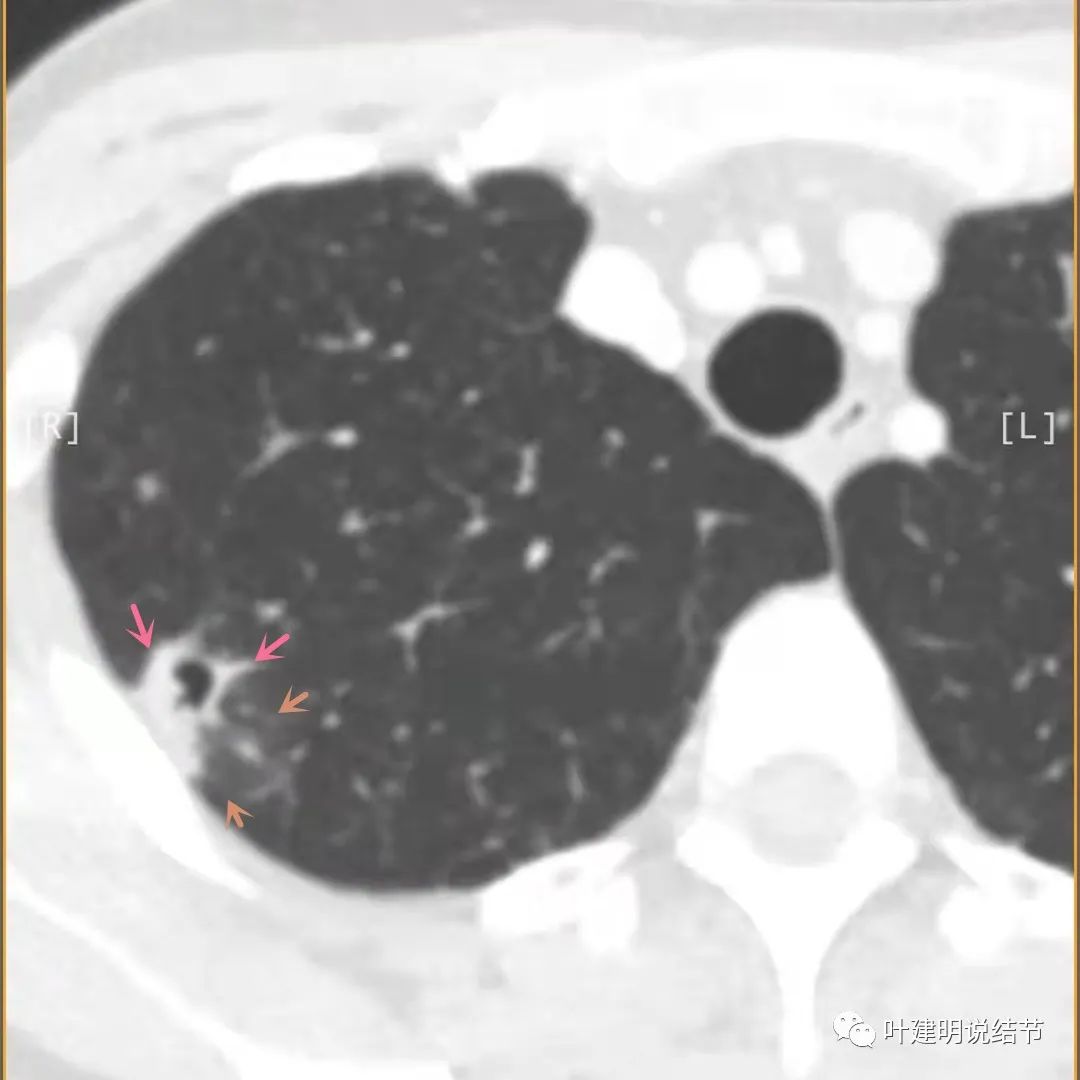

胸壁侧病灶较厚,模糊(蓝色箭头),仍见卫星灶(绿色箭头)

主病灶出现,粉色箭头示病灶密度较高,边上有磨玻璃影,甚淡(砖色箭头)

病灶有空洞(黄色箭头),主病灶边上见条索状高密度影(细红色箭头),邻近胸膜有粘连(蓝色箭头)